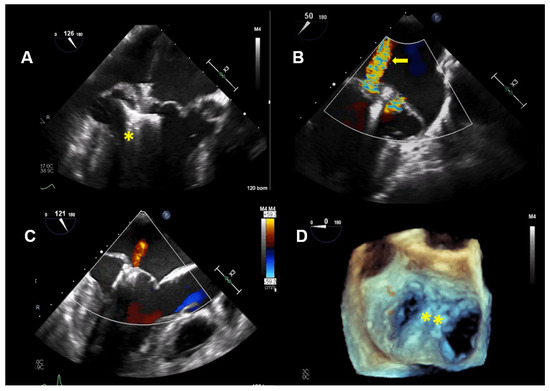

Figure 3.

Case 2: Summary of the key findings from multimodality imaging. (A) The mitral annular disjunction (yellow double arrow) is visualized in a 3D transthoracic echocardiography view. (B) A 4-chamber transesophageal echocardiographic (TEE) view shows the bi-leaflet prolapse, which is more pronounced in the posterior leaflet (yellow asterisk), thus resulting in an eccentric mitral regurgitation (MR) jet, as seen in color Doppler (right; yellow arrow). (C) The pulsed-wave Doppler profile derived in the left superior pulmonary vein shows a reverse systolic flow (yellow arrow) as a sign of severe MR. (D) Larger prolapse segments are marked with a yellow arrow in a 3D TEE view. (E) The MR is seen in a 3D TEE enface view with color Doppler. (F) Cardiac magnetic resonance imaging reveals focal mid-wall and subendocardial fibrosis in the mid-inferior wall (yellow arrows).

This patient is a 46-year-old woman with known bi-leaflet prolapse and a known MAD. She has occasional palpitations and mild dyspnea on exertion but was able to function as a yoga and Pilates instructor. She had serial TTE examinations over a period of eight years to monitor her moderate MR. Over this time period, a reduction of the LVEF from 68% to 60% was observed, as well as a slight increase of the LV-end systolic diameter from 37 to 40 mm. Brain natriuretic peptide levels were in the normal range, with 89 pg/mL.

TTE and TEE imaging confirmed the diagnosis of a bi-leaflet prolapse with myxomatous changes of both mitral leaflets (Barlow’s disease) and significant MR (Figure 3). A Zio XT patch monitor (iRhythm Technologies, San Francisco, CA, USA) showed frequent PVCs, nonsustained ventricular tachycardia (nsVT), and supraventricular tachycardia (SVT). Betablocker therapy was initiated.

CMR imaging confirmed a mildly impaired LV function (LVEF 53%) and a regurgitant fraction of 45% consistent with moderate-severe MR. The extracellular volume fraction was 34% (normal limit <30%), consistent with diffuse myocardial fibrosis. Focal mid-wall and subendocardial fibrosis was observed in the mid-inferior wall (Figure 3F).

Thus, based on all of the findings, an increased perioperative morbidity in this MR patient was hypothesized and, also, to comply with the patient not wanting surgery, the decision was made to proceed with a percutaneous MV repair strategy. Subsequently, two MitraClips (XTR) (Abbott Vascular, North Chicago, Illinois, USA) were implanted with an excellent result, with minimal residual MR (Figure 4). One year after MitraClip implantation, the patient reported significantly fewer palpitations, and her exercise tolerance was normal. TTE imaging documented normal LV function with a LVEF of 60%, normal pulmonary artery systolic pressure and mild, late-systolic MR. Using Zio XT patch monitoring, a marked reduction in PVCs from 18.7% to 1.2% and rare SVT were seen, and no nsVT occurred (data are in Figure 5).

Figure 4.

Case 2: Procedural transesophageal echocardiographic imaging during MitraClip XTR (Abbott Vascular, North Chicago, Illinois, USA) implantation. (A) The first MitraClip XTR (yellow asterisk) is positioned below the mitral leaflets with opened Clip arms. (B) Residual mitral regurgitation (MR) after implantation of the first Clip is marked with a yellow arrow. (C) After positioning of the second Clip, only mild MR is present. (D) The 2 MitraClip XTR devices (yellow asterisk), which create a double orifice, are seen in a 3D enfaced view.